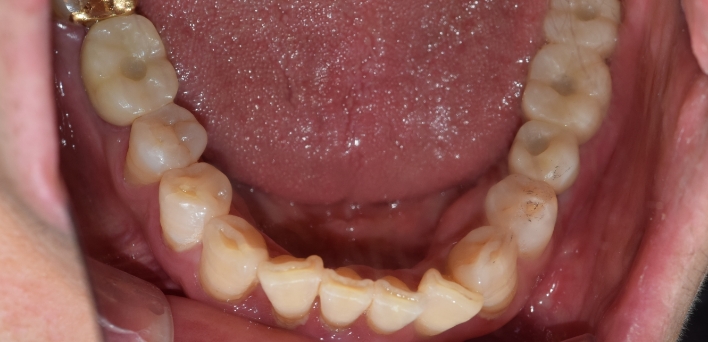

임플란트 : 손 ** 님 (50대)

치아가 있다는게, 아직도 정말 꿈만 같아요.

Before Before

2020.02.30

After After

※ 더서울치과의원은 의료법을 준수하며 위 케이스는 실제 환자의 동의를 얻은 사례로 치료 전, 후가 동일한 환경에서 촬영되었습니다.

환자 케이스에 따라 부작용이 발생할 수 있습니다. 이 부분은 의료진의 충분한 상담과 체크를 통해 예방하고 줄일 수 있습니다.

[임플란트 부작용] 수술 후 관리가 소홀할 경우 출혈, 주위염 등의 부작용이 발생할 수 있어 구강 위생을 철저히 유지하고, 정기적인 검진을 통해 상태를 점검하는 것이 중요합니다.

환자 특징

환자 특징01무치악 상태

환자 특징02수년간 무치악으로 지내심

임플란트가 불가능할것이라

생각하고 내원

위, 아래 6개씩 식립

디지털 풀아치 임플란트